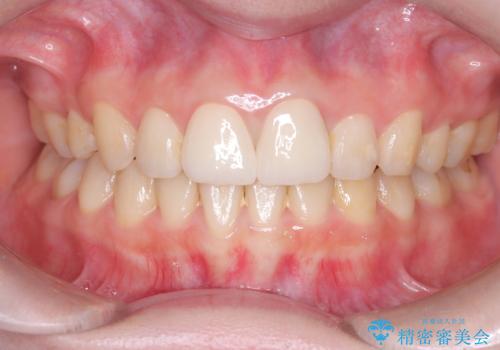

突き出た前歯を下げて理想的な横顔に。上下左右4番抜歯による審美ワイヤー矯正

担当医 河口智英